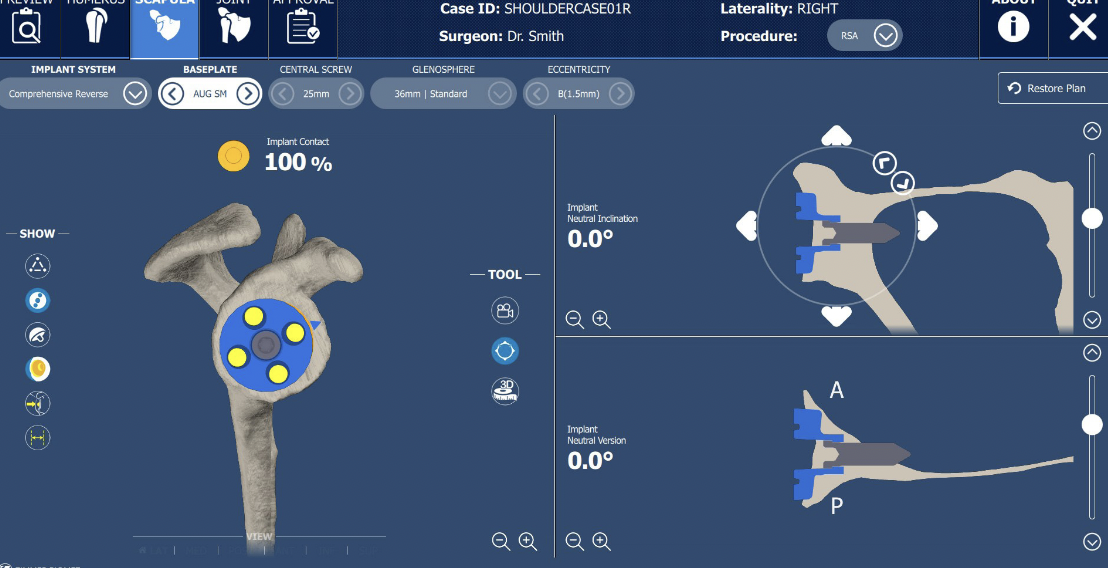

CT templating

Zimmer Trabecular metal rTSA CT templating

Zimmer Signature One CT templating pdf

- systematic review of use of computer assisted navigation in rTSA

- increases accuracy baseplate screw placement

- allows longer screws and better purchase

- systematic review of computer assisted navigation in rTSA

- improves inclination of the baseplate

- increases use of augmented implants

- increases surgical time